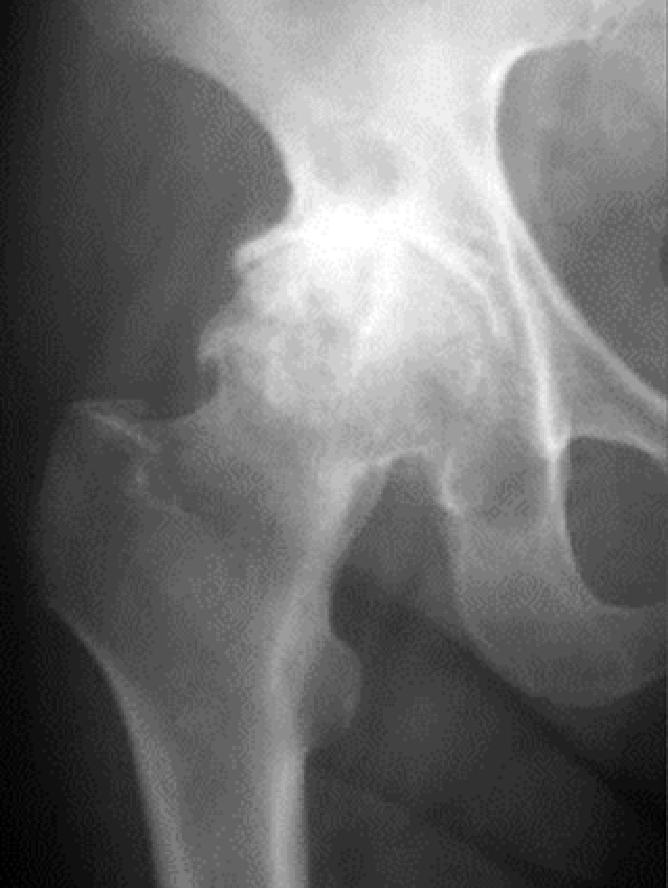

主な股関節症には、変形性股関節症(図4)、大腿骨頭壊死症(図5)、関節リウマチ(図6)などがあります。

図4. 変形性股関節症

図6. リウマチ性股関節症